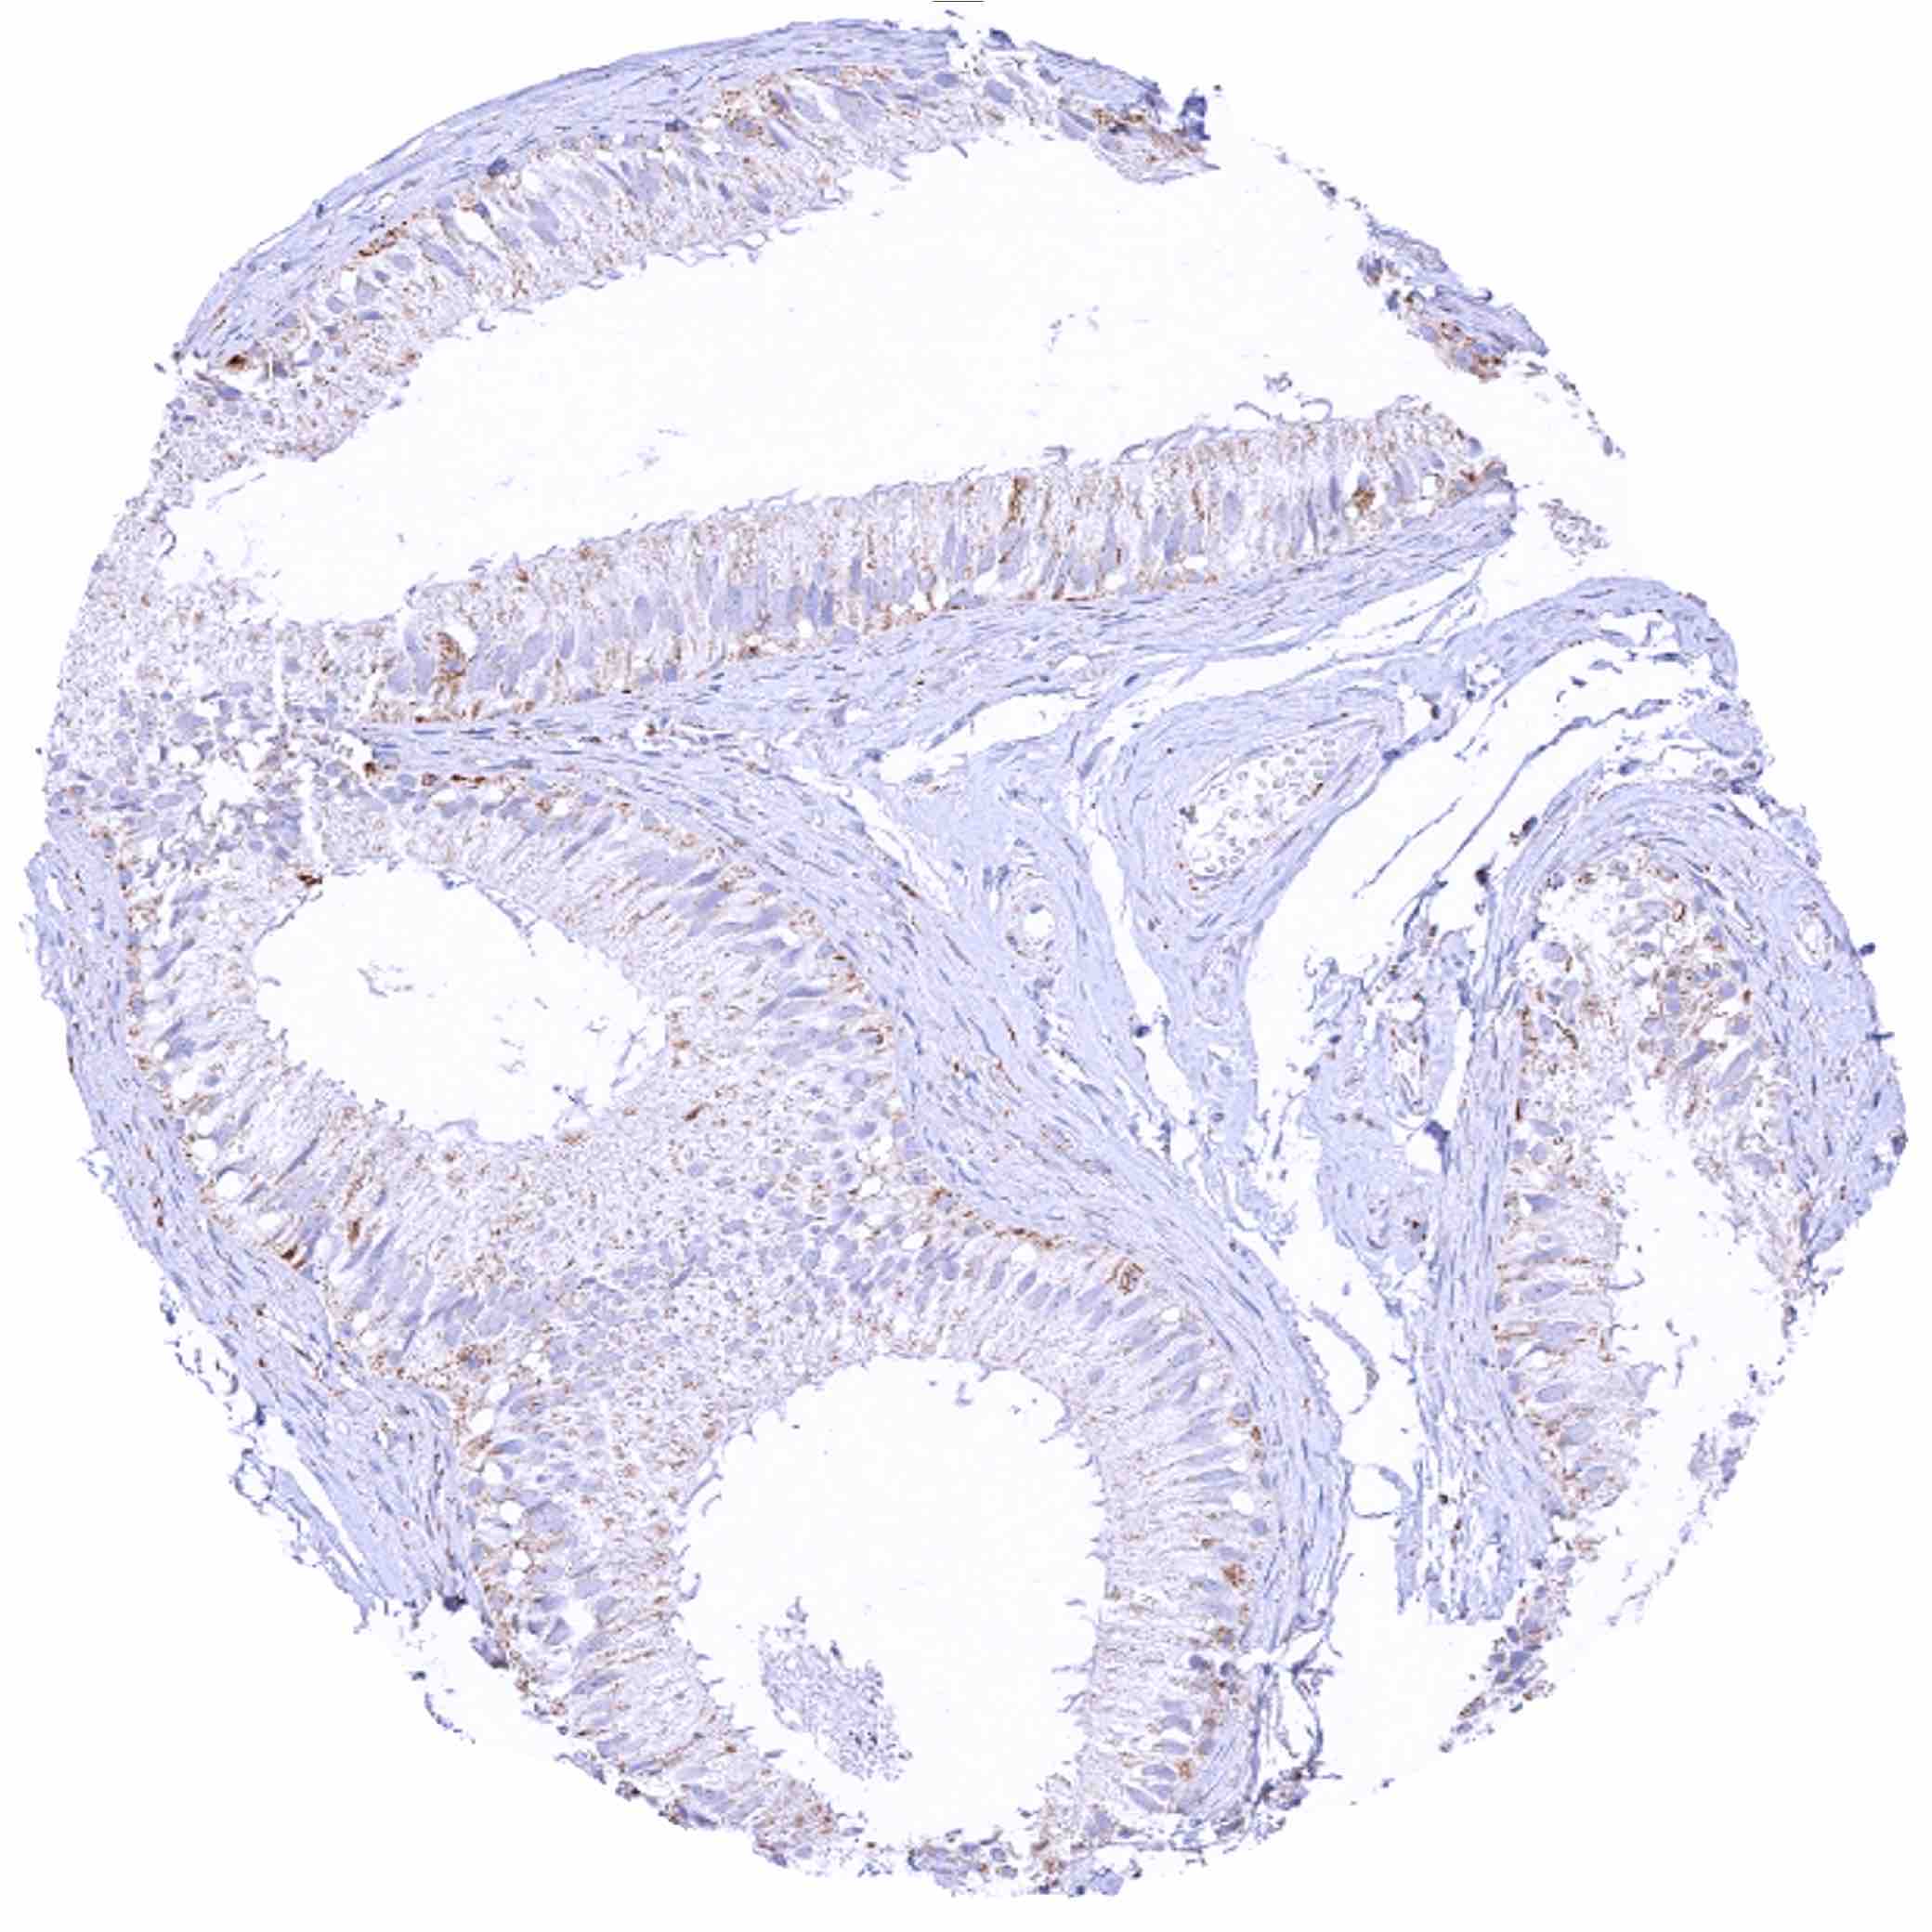

Appendix, mucosa – At least a moderate granular cytoplasmic SDHB staining of all cells, predominantly in the epithelium

Appendix, muscular wall – Weak granular cytoplasmic SDHB staining of smooth muscle cells